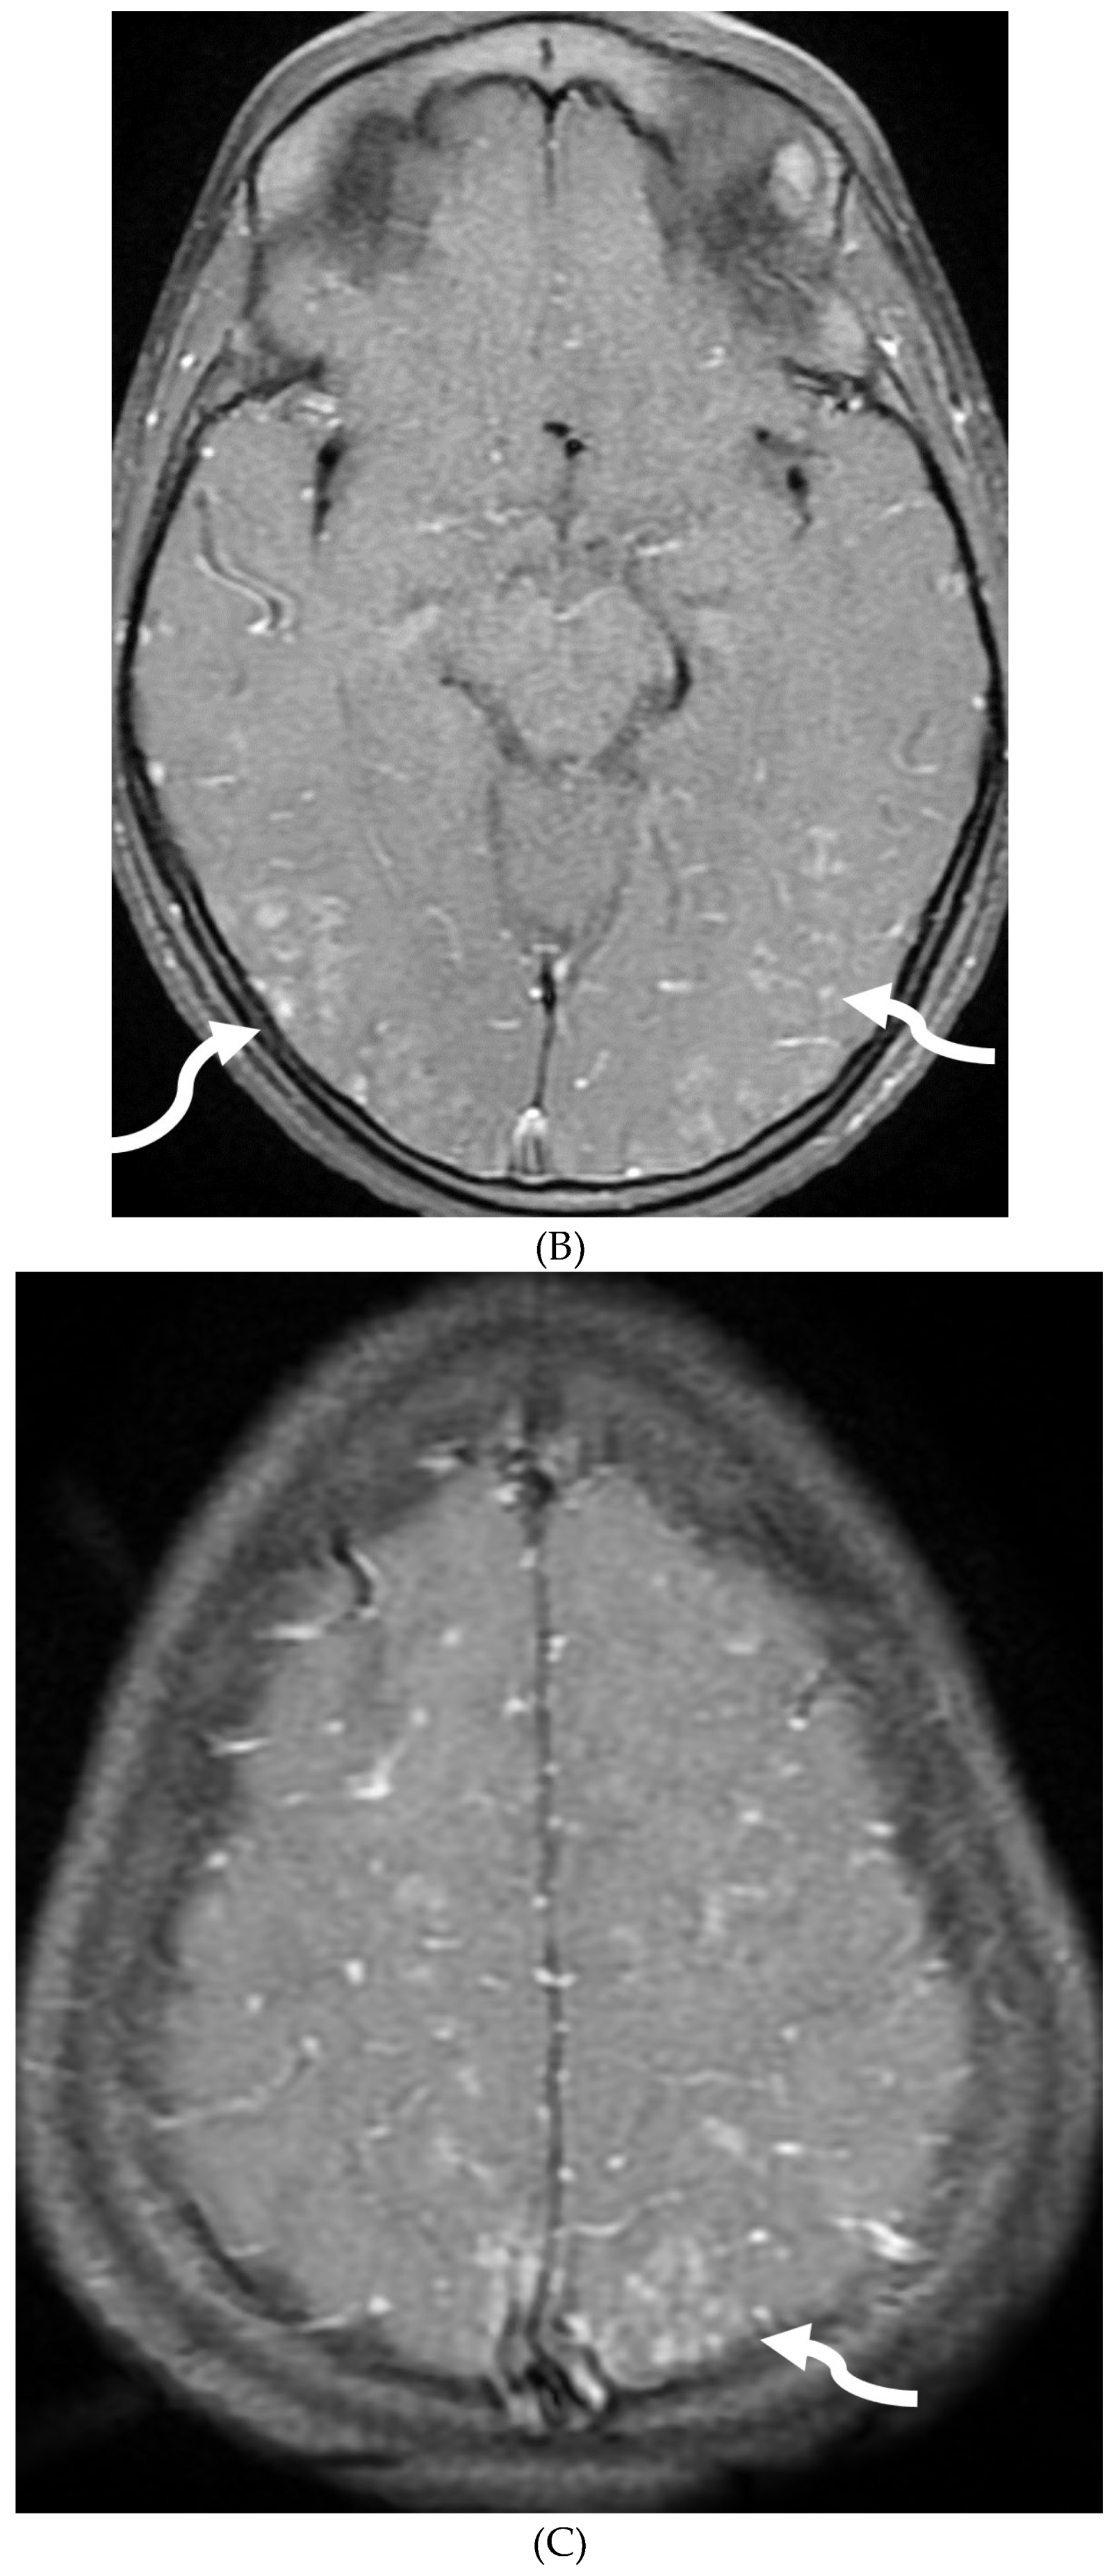

INTRACRANIAL HYPOTENSION (IH)

- Peterson EE, Riley BL, Windsor RB. Pediatric Intracranial Hypotension and Post-Dural Puncture Headache. Semin Pediatr Neurol. 2021 Dec;40:100927. Epub 2021 Sep 3. PMID: 34749914. [CrossRef]

- Schievink WI, Maya MM, Louy C, Moser FG, Sloninsky L. Spontaneous intracranial hypotension in childhood and adolescence. J Pediatr. 2013 Aug;163(2):504-10. Epub 2013 Feb 28. PMID: 23453548. [CrossRef]

- Shah LM, McLean LA, Heilbrun ME, Salzman KL. Intracranial hypotension: improved MRI detection with diagnostic intracranial angles. AJR Am J Roentgenol. 2013 Feb;200(2):400-7. PMID: 23345364. [CrossRef]

- Yuh EL, Dillon WP. Intracranial hypotension and intracranial hypertension. Neuroimaging Clin N Am. 2010 Nov;20(4):597-617. PMID: 20974378. [CrossRef]

- Medina JH, Abrams K, Falcone S, Bhatia RG. Spinal imaging findings in spontaneous intracranial hypotension. AJR Am J Roentgenol. 2010 Aug;195(2):459-64. PMID: 20651205. [CrossRef]